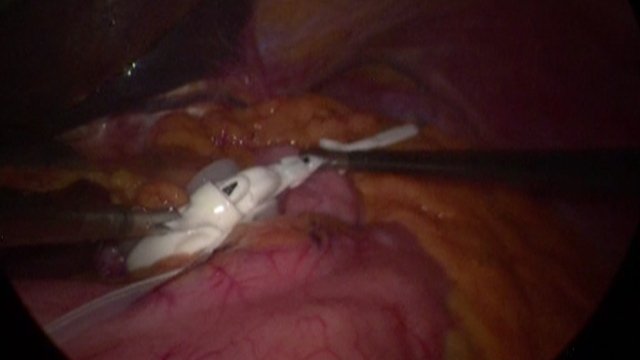

• Laparoscopic sleeve gastrectomy

• Sleeve gastrectomy